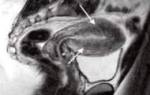

Для того чтобы диагностировать заболевание, мало пройти УЗИ, поскольку аденомиоз слишком похож на миому матки, а часто и сопровождает ее. Необходимо пройти гистероскопию для более точных результатов.